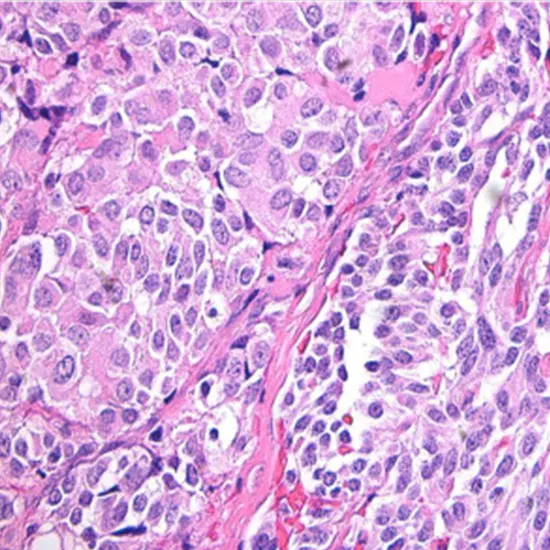

medullary thyroid carcinoma

Medullary thyroid carcinoma (MTC) is a rare type of thyroid cancer that arises from the parafollicular cells, also known as C cells, which are responsible for producing calcitonin, a hormone that regulates calcium levels in the body. MTC accounts for approximately 1-2% of all thyroid cancers.